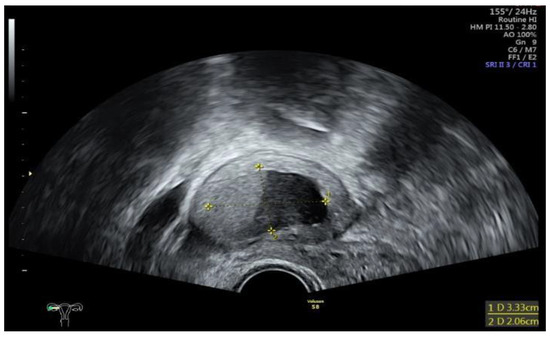

Data collection: The patients’ backgrounds, clinical symptoms at admission, sonographic and laboratory assessment, as well as intraoperative findings were recorded. Patient demographic data included age, menopausal status, presence of dysmenorrhea, history of endometriosis surgery, and use or non-use of hormonal downregulation therapy for endometriosis. Pre-operative laboratory tests included white blood cell (WBC) count, serum C-reactive protein (CRP) level, and serum CA125 level, and all patients underwent transvaginal sonography (Figure 1) on admission as part of the emergency diagnostic assessment. The maximal diameter and the location of the endometriomas were noted. The intraoperative findings included the location of the ruptured endometriomas (Figure 2 and Figure 3), the presence and classification of endometriosis according to the rASRM [16] and #ENZIAN [17] systems, and, lastly, total blood loss.

Figure 2. Intraoperative laparoscopic display of a ruptured endometrioma of the left ovary in a 43-year-old woman.